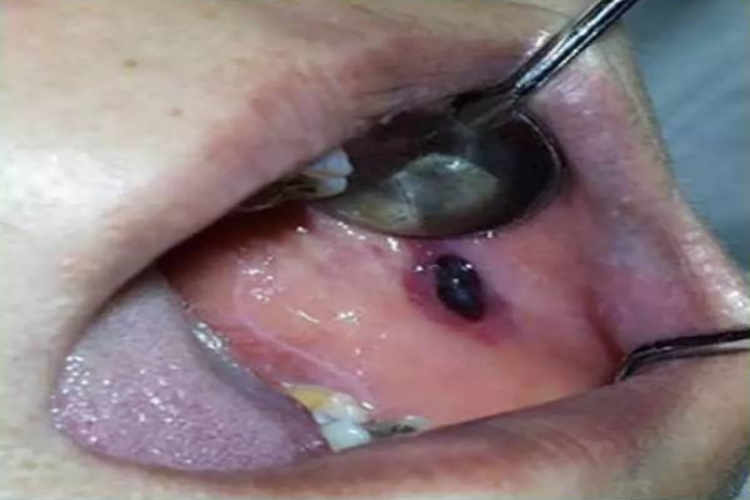

黏膜血疱

初起疱液鲜红,旋即变为紫黑色,表面凸起,肉眼可见为黑点,疱壁薄,容易破裂,淤血流尽后留有鲜红色疱底创面,疼痛明显,影响吞咽。一般愈合较快,有继发感染则形成糜烂或溃疡。